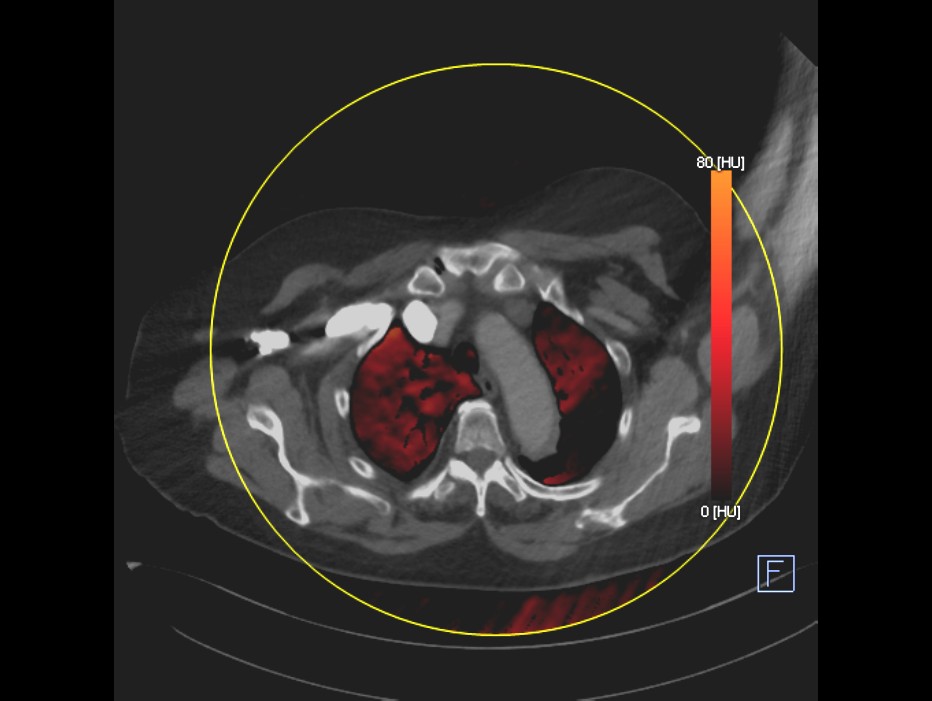

Dual Enerji Bt İle Üriner Sistem Taşlarında Analiz

Üriner sistemde taşların yapısı hidroksiapatit, sistin, ürik asit , oksalat taşı, mikst taş gibi

BT ortamında yapılmaktadır.  Böylelikle laboratuar ortamına gerek kalmadan taşın yapısı ve taş kırma yöntemi ile tedavi olup olamayacağı kararı verilmektedir.,